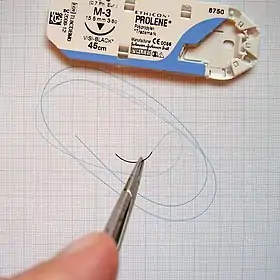

| Surgical needle |  |

accessories and implants | |

| Suture |  |

||